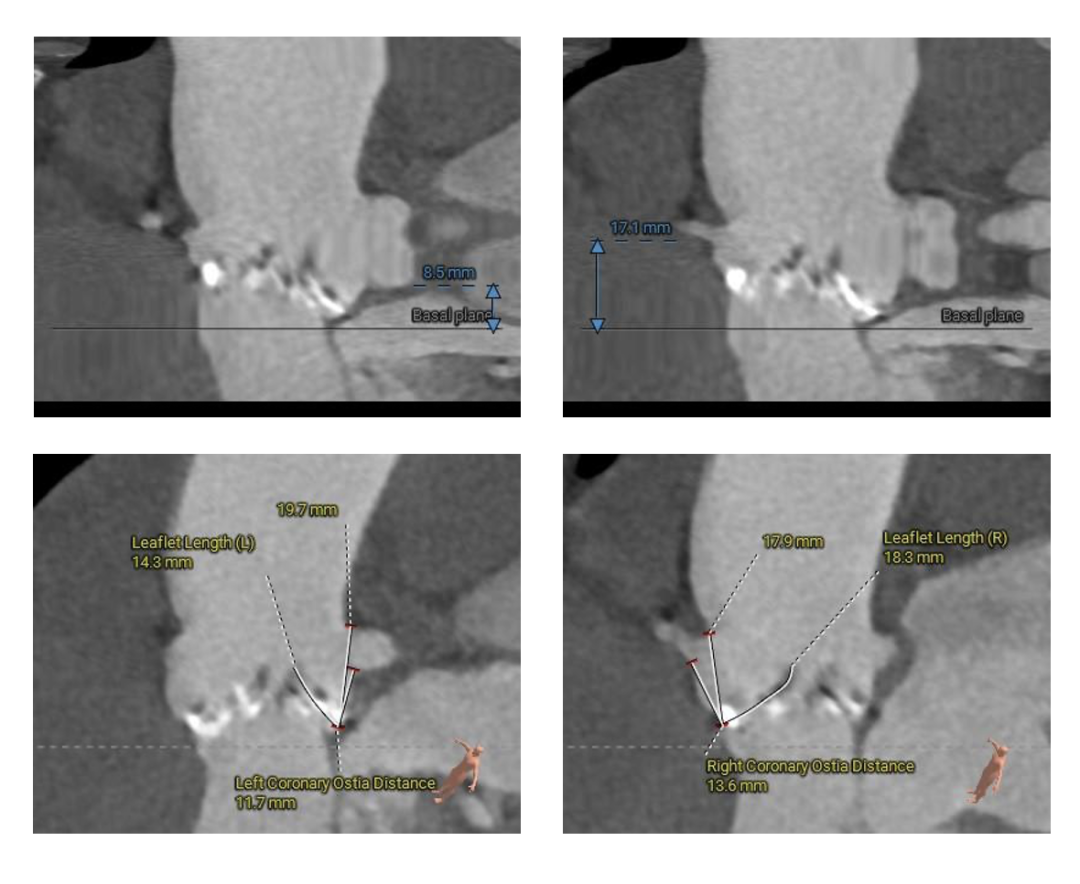

术前CT评估

主动脉根部测量

冠脉测量

Type-0型二叶瓣,中-重度钙化伴瓣叶增厚,左冠开口高度偏低,右冠开口高度可,左冠瓣叶长度略大于冠脉开口上缘与瓣叶附着缘距离,左室流出道整体呈直筒型,瓦氏窦,窦管交界,升主动脉内径可,左室腔内径可,心室壁增厚,主动脉瓣环与水平面夹角51度,非横位心,主动脉弓距、弓角可 -双侧入路血管走形良好,整体入路条件可

使用沛嘉20mm球囊预扩,预装沛嘉TaurusElite AV23瓣膜,释放高度瓣上0-2mm